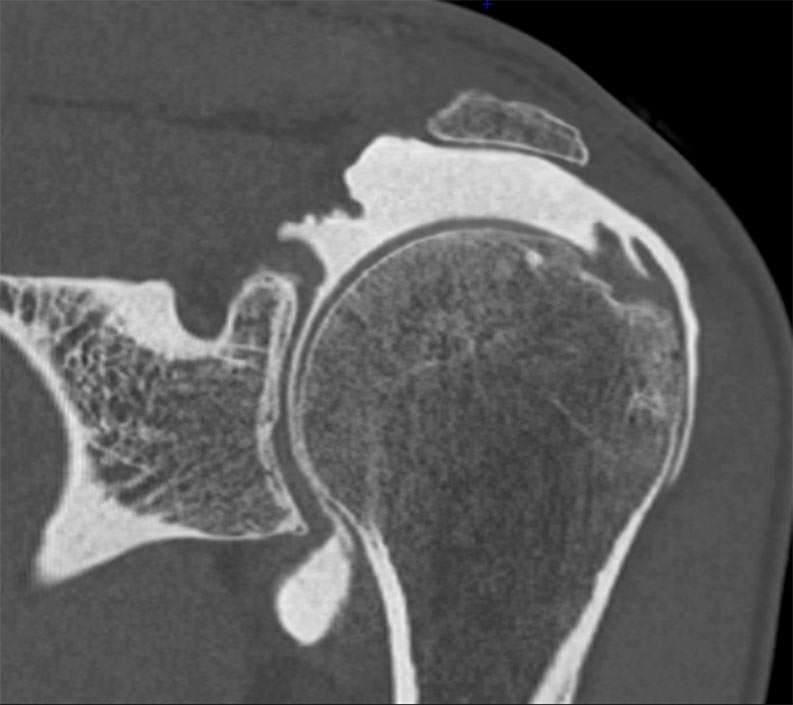

Shoulder Right

Patient 76 y/o, Male, right-handed

• 03/2021: Supraspinatus + Infraspinatus double-row repair (Dr. Laurent LAFOSSE)

• 06/2021: Revision SSP+ISP double-row repair (Dr. Laurent LAFOSSE)

• 12/2024: Pain and weakness in ER2